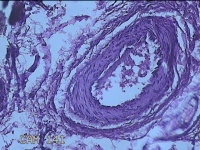

外阴部包块

性别

女

年龄

37岁

临床诊断

皮脂腺囊肿

一般病史

外阴部起包块一月余。

标本名称

大体所见

灰白暗红色包块2.3x1.8x0.8cm一个,表面糜烂,切开包块呈实性,切面灰白淡黄色,质软。

图1